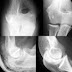

Fracturas extra-articulares de la rodilla - Clasificación de Salter y Harris

Está en parte basada en la clasificación preconizada 65 años antes por J. Poland y, en ella, se distinguen cinco grandes grupos (Fig. 1):

• Tipo I.

Similar al grupo I de Poland y consiste en una separación completa epifiso-metafisaria, normalmente como resultado de la aplicación de fuerzas de avulsión o cizallamiento.

• Tipo II.

Es el tipo más común de fractura fisaria. Es muy parecido al tipo I pero, en ésta, el trazo de fractura, después de transcurrir a lo largo de la mayor parte de la fisis se adentra en la metáfisis, quedando por tanto un pequeño fragmento de la misma, generalmente triangular, unido a la fisis y epífisis (signo de Thurston Holland). Generalmente estas fracturas se producen por la combinación de fuerzas de flexión lateral (varo valgo) y cizallamiento.